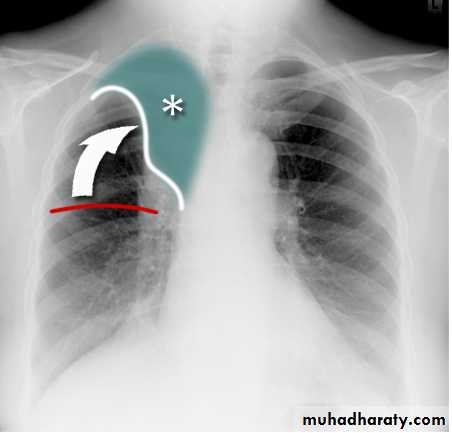

Pleural Effusion on Chest Radiographs.

Posteroanterior (A) and lateral (B) chest radiographs demonstrate the typical meniscoid appearance (arrows) in a patient with a left pleural effusionHydropneumothorax.